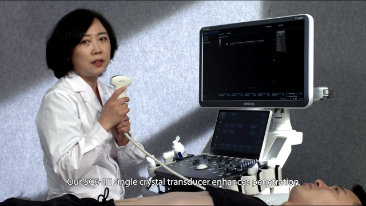

Sinds de oprichting van het bedrijf is Mindray voortdurend op zoek naar nieuwe manieren om het diagnostisch vertrouwen te vergroten. Resona 7 wordt aangestuurd door de meest revolutionaire ZONE Sonography?-technologie. Zijn nieuwe ZST+-tilt de kwaliteit van ultrasoundbeeldvorming naar een hoger niveau door middel van zoneacquisitie en kanaalgegevensverwerking.

Naast de hoogwaardige beeldvormingskwaliteit verbetert de Resona 7 tevens de klinische onderzoeksmogelijkheden met de revolutionaire V Flow voor vasculaire hemodynamische evaluatie, en de intelligentste vlakacquisitie van een 3D-gegevenssets voor de diagnose van het foetale, centrale zenuwstelsel. Met zijn combinatie van de meest intu?tieve, op vingerbewegingen gebaseerde multi-aanrakingsbediening en alle essenti?le klinische functies loopt de Resona 7 voorop in de nieuwe golven van ultrasoundinnovatie.